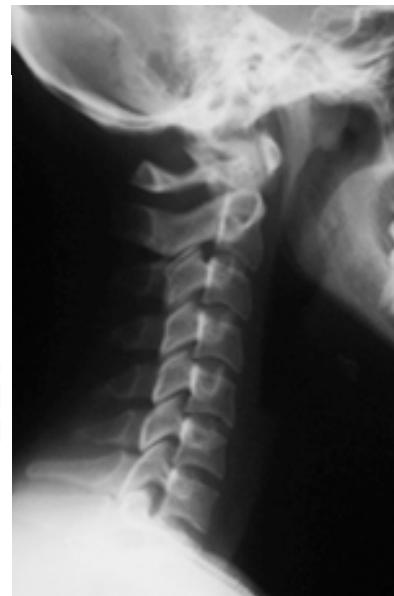

Cervical Spine Radiographs

Lateral View:

- All C-vertebrae & upper T1

- Prevertebral soft tissue width

- Four parallel curves:

- Front of vertebral bodies

- Back of vertebral bodies

- Posterior borders of lateral masses

- Bases of spinous processes